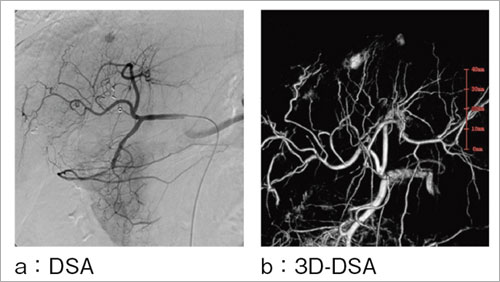

肝細胞がんの栄養血管の同定には,カテーテルによる選択的造影が行われる。その際,複雑な血管を判断するために立体的な観察が有効な場面がある。そのため,正面側からの撮影だけではなく,斜位にCアームを配置して観察するようなこともあった。

また,複雑な血管構造を理解するため,回転DSAによる観察も検討され,IVR支援機能として利用いただいた1)。回転DSAでは,撮影方向以外の立体観察ができないという弱点がある。そのため,一度の撮影で多方向から観察できるアプリケーションが望まれた。

その結果,回転撮影して得られた画像をもとに三次元再構成する3D-Angioが登場した。3D-Angioは,頭頸部を中心に標準的なアプリケーションとなったが,腹部領域においても栄養血管の同定に有効である。Infinix Celeve-iでは,回転DA,回転DSAのどちらからも三次元再構成が可能である。特に回転DSAからの再構成画像では,造影剤の入った血管像のみを再構成するため,造影剤に染まった肝細胞がんと栄養血管を明瞭に確認できる。図4に3D-DSAの一例を示す。 |

図4 3D-DSA:肝細胞がん |